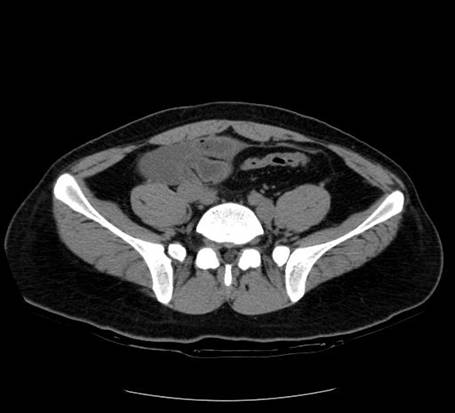

以下是引用zsl6918在2007-6-22 21:08:00的发言:[br]病史较长,反复发作,基本排除恶性病变,腹部定位像可见是小肠梗阻征象,原因无非是肠源性,血管性和神经性的,肠源性的在排除占位后应想到 肠旋转不良的可能,血管性的应想到肠系膜血管的栓塞,神经性的要想到植物神经功能紊乱的可能,本病例应该强化检查帮助诊断,个人感觉旋转不良可能性大。

以下是引用青莲居士在2007-6-24 12:27:00的发言:[br]肠梗阻[br]肝内胆管结石